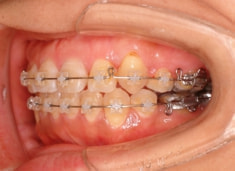

治療開始から約1年2ヶ月後